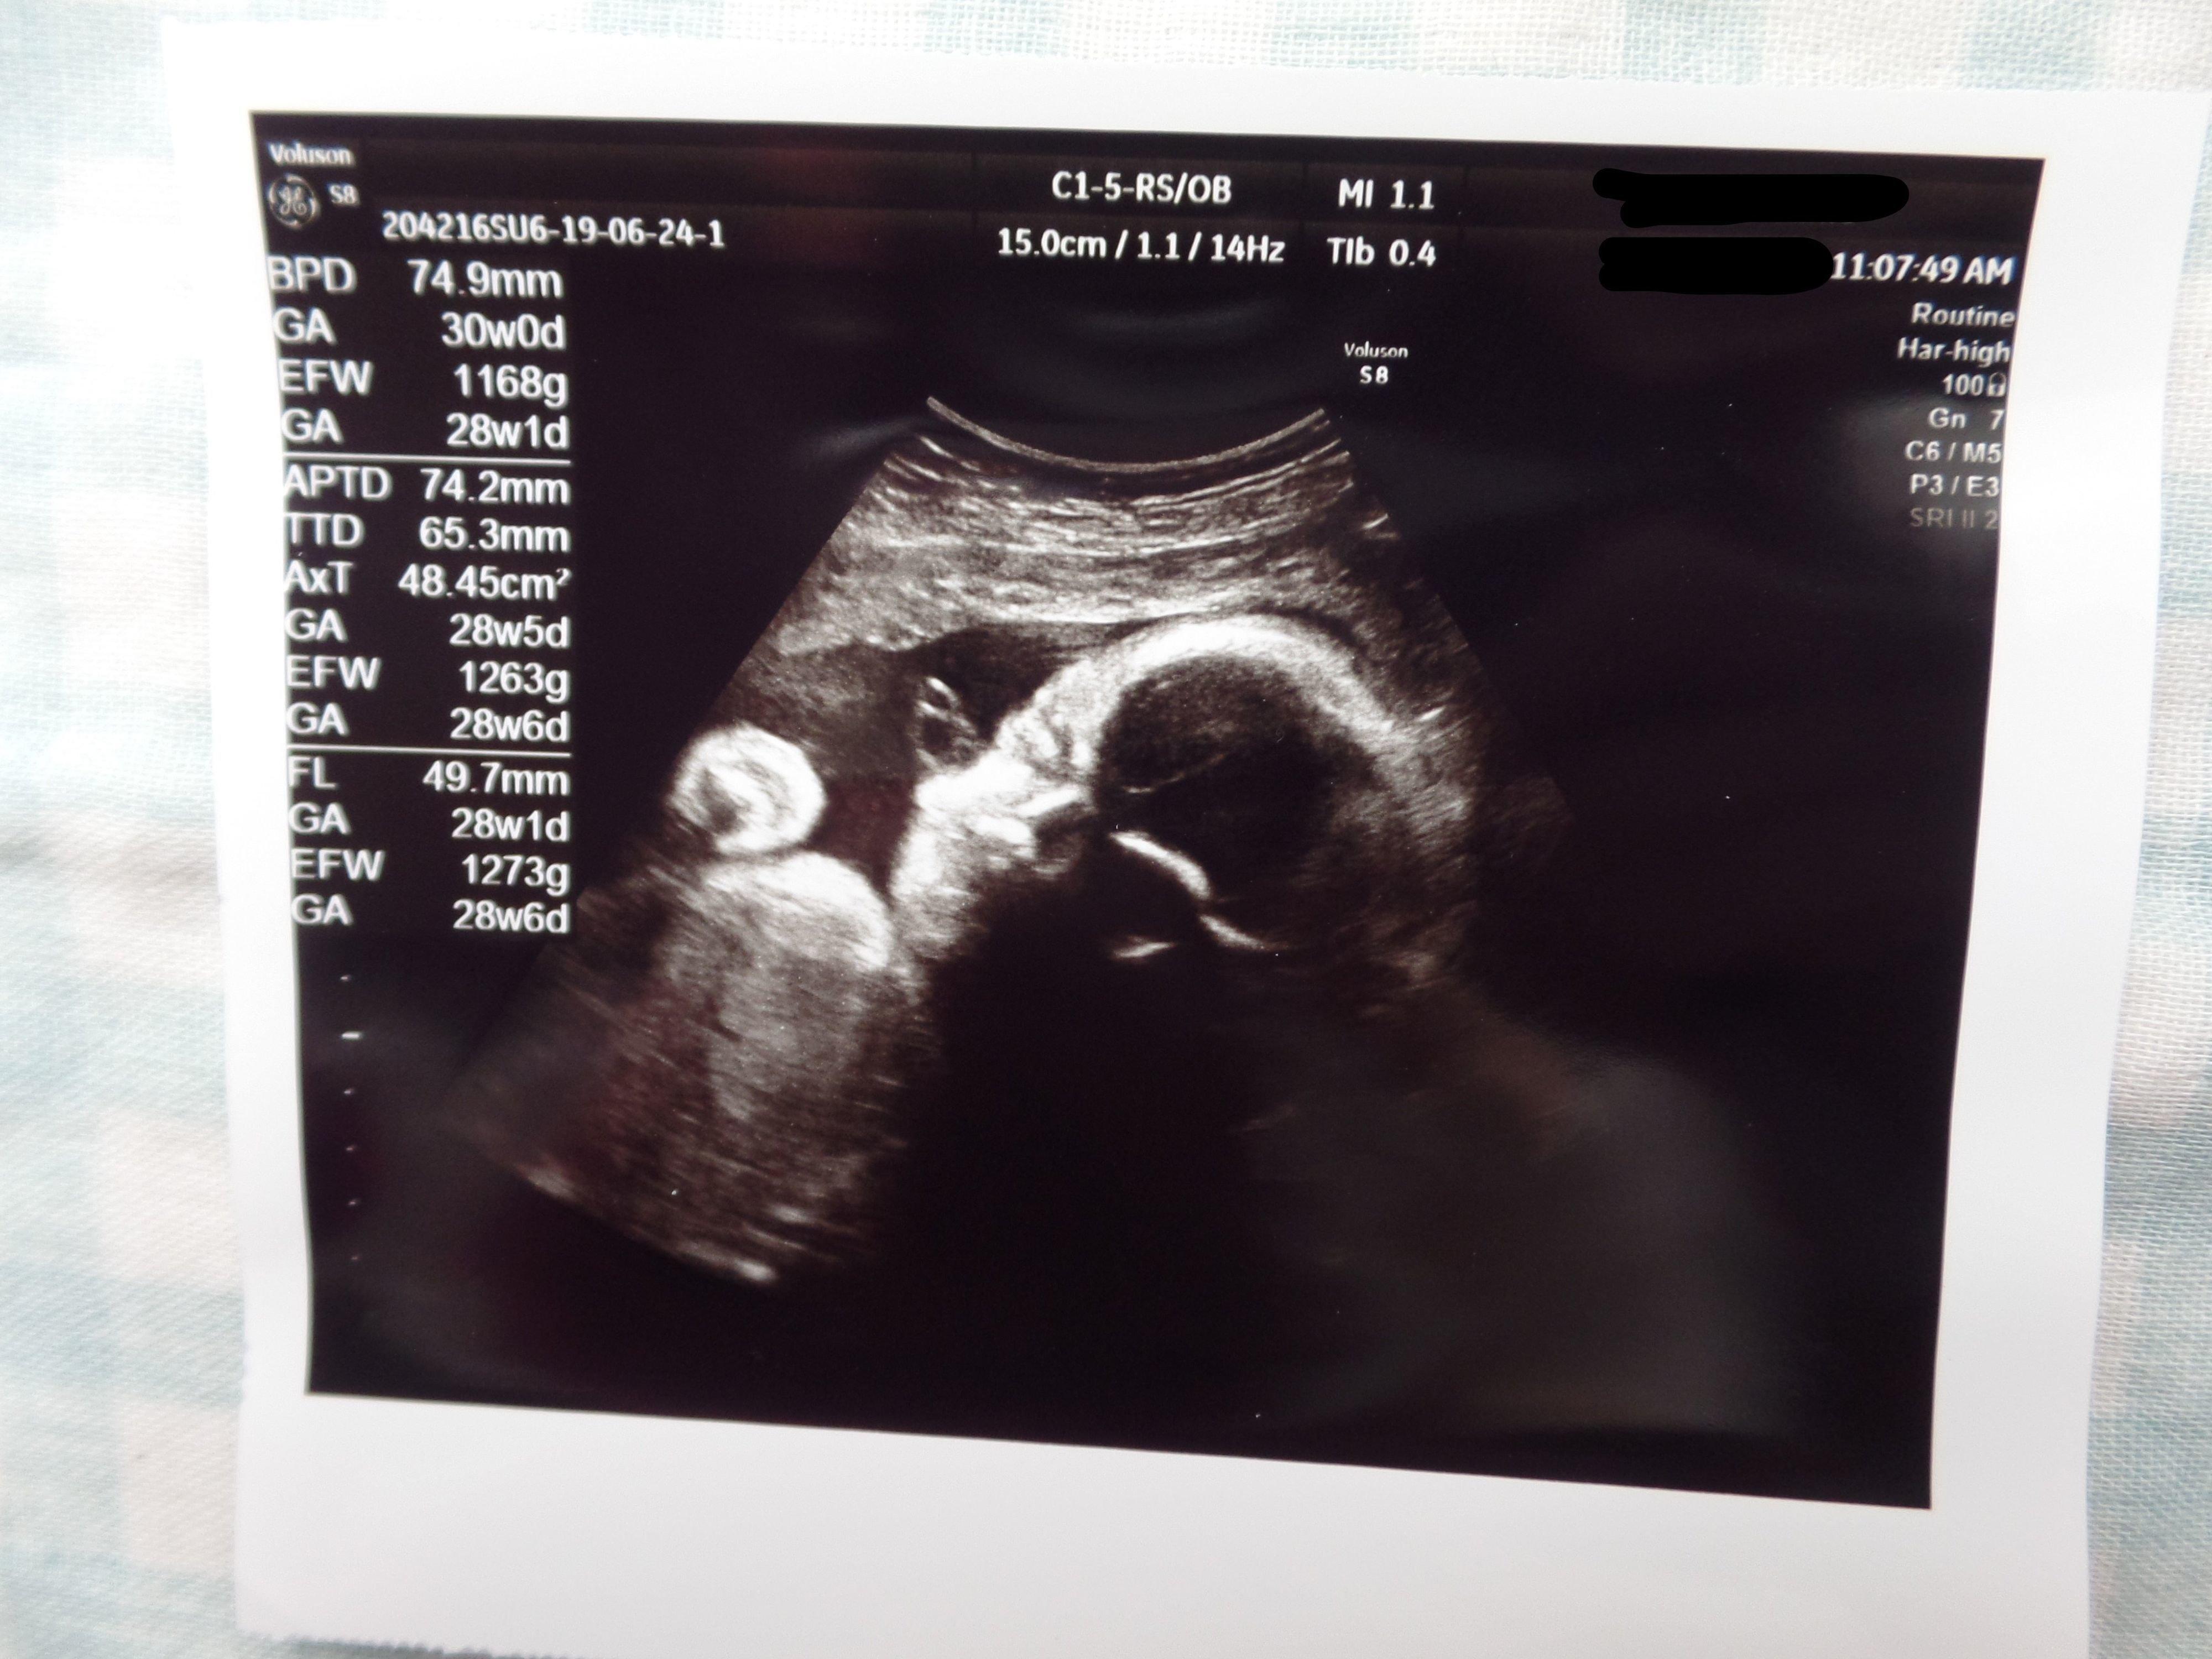

3. 多嚢胞性卵巣症候群(PCOS)から不妊治療を経て高齢出産! エコー写真で喜びを振り返る